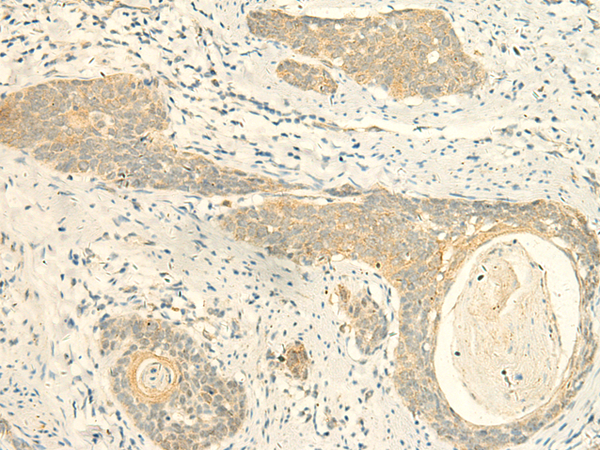

分类: 科研抗体货号: P10037别名: PP2CB; PP2CBETA; PP2C-beta; PPC2BETAX; PP2C-beta-X应用: IHC反应种属: Human